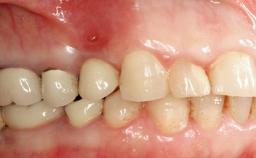

Peripheral Giant-cell Granuloma Associated with Peri-implant Tissues

Giant-cell granulomas (GCG) of the jaws are benign reactive lesions of unknown etiology, unrelated to giant-cell tumors (osteoclastomas), which are defined as benign but locally destructive and aggressive neoplasms (Jundt and coworkers 2005). Depending on their localization at the initial diagnosis, GCG are dived into central (CGCG) and peripheral (PGCG) types. CGCGs occur within the jawbones and appear as unilocular or multilocular radiolucent lesions. The incidence in the general population is very low. They are more commonly found in the mandible, mainly in children and young adults—patients are generally younger than 30 years—and have a greater incidence in females (Heithersay and coworkers 2002). The clinical behavior of CGCGs varies from slowly growing asymptomatic swellings to aggressive lesions that may result in pain, cortical perforation of the affected jaw site, and root resorption (de Lange and coworkers 2007).